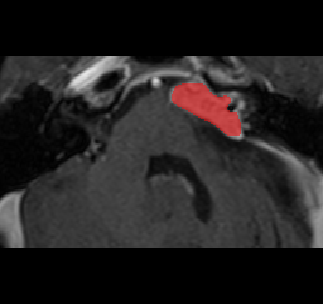

Recently, deep learning methods have achieved state-of-the-art performance in many medical image segmentation tasks. Many of these are based on convolutional neural networks (CNNs). For such methods, the encoder is the key part for global and local information extraction from input images; the extracted features are then passed to the decoder for predicting the segmentations. In contrast, several recent works show a superior performance with the use of transformers, which can better model long-range spatial dependencies and capture low-level details. However, transformer as sole encoder underperforms for some tasks where it cannot efficiently replace the convolution based encoder. In this paper, we propose a model with double encoders for 3D biomedical image segmentation. Our model is a U-shaped CNN augmented with an independent transformer encoder. We fuse the information from the convolutional encoder and the transformer, and pass it to the decoder to obtain the results. We evaluate our methods on three public datasets from three different challenges: BTCV, MoDA and Decathlon. Compared to the state-of-the-art models with and without transformers on each task, our proposed method obtains higher Dice scores across the board.